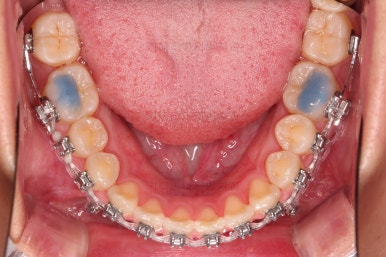

아랫니 틈은 거의 없어졌네요.

대신 여러 교합적인 이유로 아랫니를 좀 더 앞으로 당겨주긴 해야 합니다.

이제 마무리를 해봅니다.

교합 양호하고 치아 사이 틈새도 잘 모아졌습니다.

특히나 틈새가 있었던 환자분의 교정치료는 재발을 할 우려가 크므로 원인 요소가 되는 부분들을 잘 찾고 개선해주며 유지장치도 좀 더 광범위하게 부착해 줍니다.